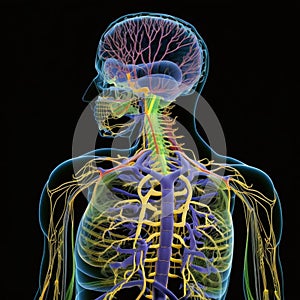

The AI-generated image is a schematic depiction of the human nervous system, featuring the brain, spinal cord, and peripheral nerves. The brain is shown at the top of the image, with the spinal cord extending downwards. Branching out from the spinal cord are the peripheral nerves, which are shown in various colors to indicate their different functions. The image has a clean and modern aesthetic, with bold lines and geometric shapes used to convey the different elements of the nervous system. The color palette is primarily shades of blue, emphasizing the importance of this system in controlling bodily functions. Overall, the image provides a clear and concise overview of the key components of the human nervous system, making it a useful tool for educational and medical purposes.